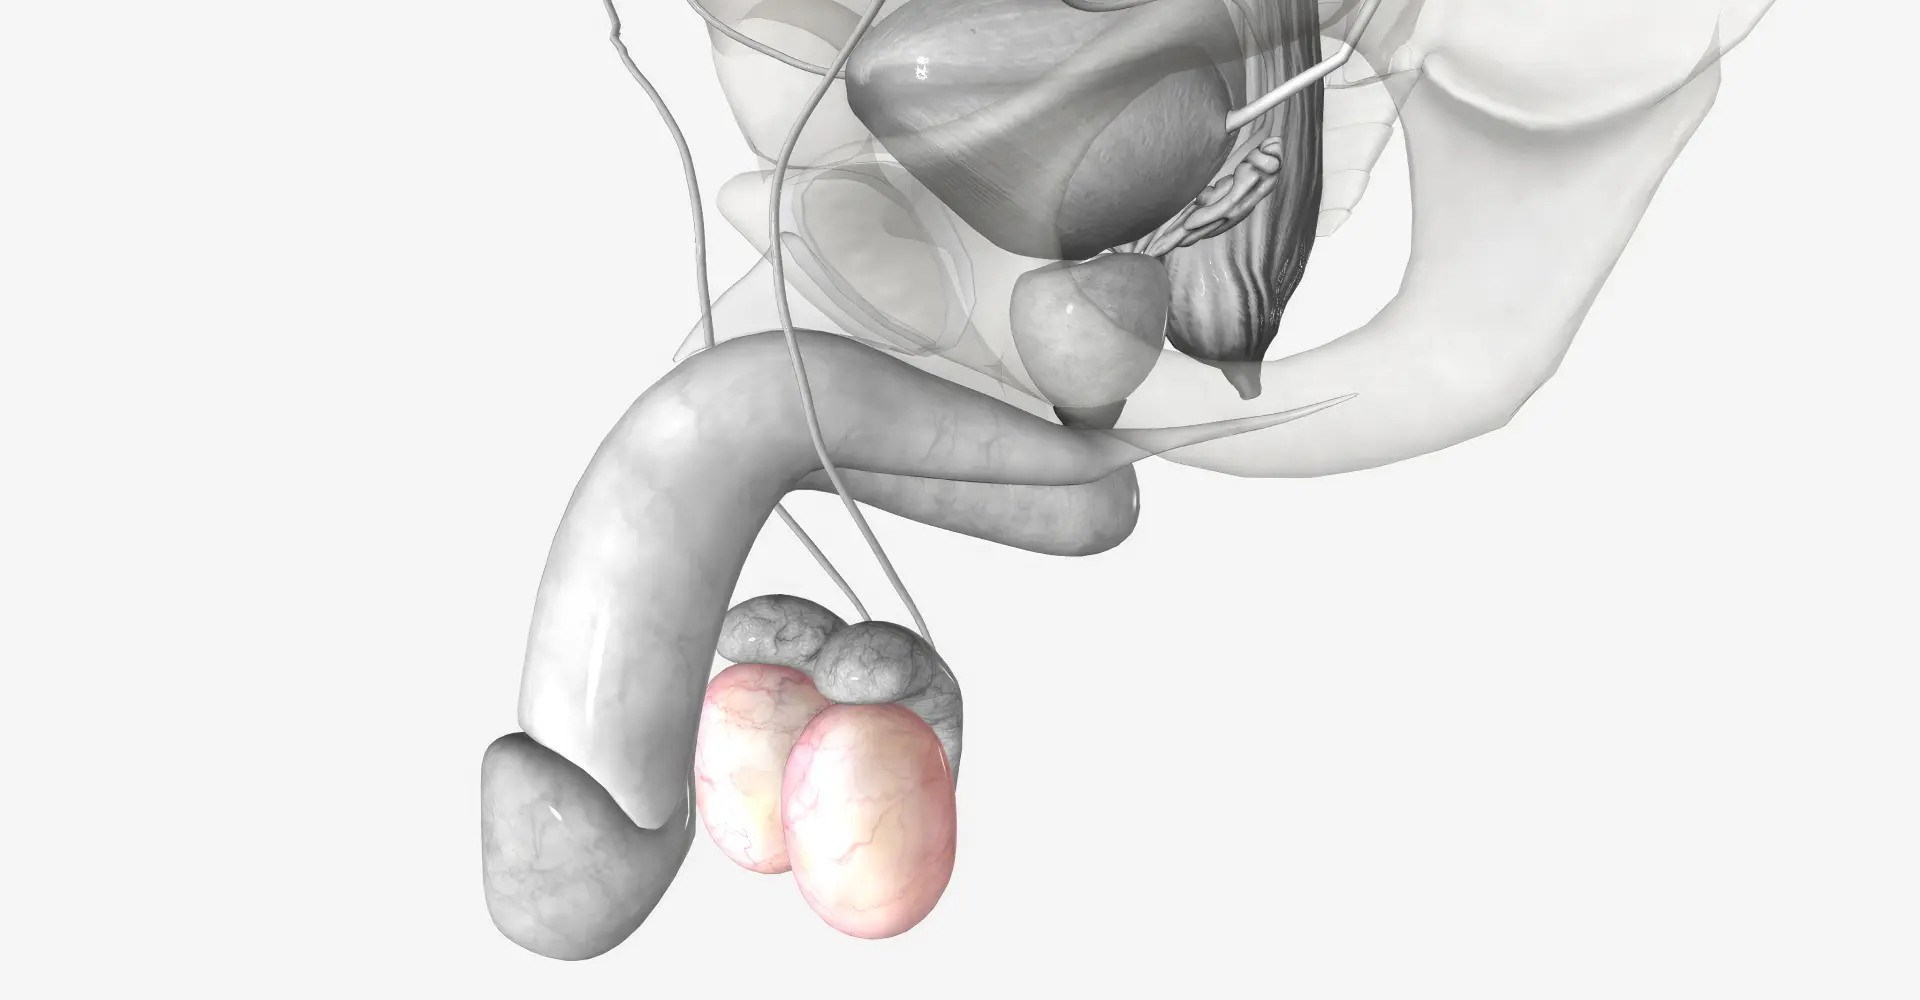

Entre os tipos de próteses, as principais são as semirrígidas e as infláveis. A escolha do modelo depende de fatores individuais e o paciente deve fazê-la com orientação médica especializada. As próteses semirrígidas oferecem rigidez constante, enquanto as infláveis podem ser controladas conforme a necessidade. Ambas são projetadas para serem confortáveis e duradouras, garantindo que o paciente se sinta seguro e satisfeito com a decisão. Ao escolher a prótese peniana ideal, o paciente encontra uma opção que realmente transforma sua vida e assegura uma vida íntima ativa e saudável.